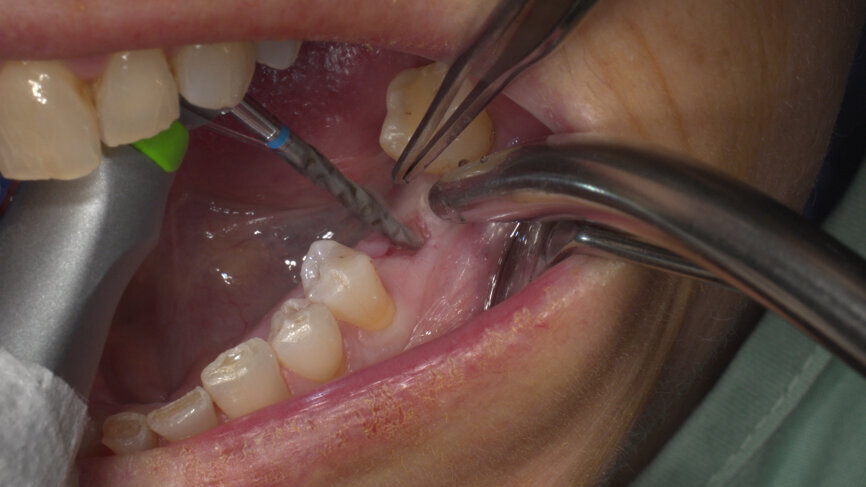

Under local anaesthesia, a flapless implant surgery technique was performed in position #36. Owing to the quality of the bone, staged drilling with continuous saline irrigation was performed in order to obtain a proper, safe insertion torque (Figs. 2–7). One implant (BLT, Regular Neck, Roxolid, ⌀ 4.8 × 10.0 mm) was placed, and a torque of 42 N cm was applied (Figs. 8–11).